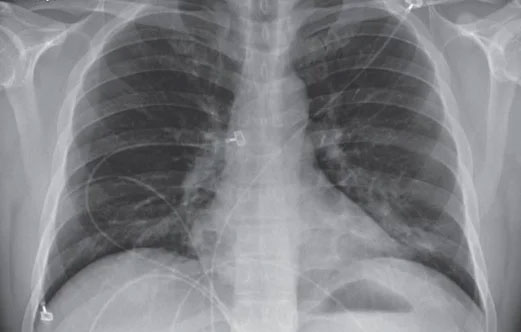

Hình ảnh lưới và đông đặc nền phổi hai bên trên X-quang phổi thẳng của bệnh nhân Covid-19. (Ảnh: BVTWQĐ108).

Một số cuộc nghiên cứu ngay từ giai đoạn đầu của đại dịch cũng cho thấy trong hình ảnh chụp X-quang lồng ngực của bệnh nhân nhiễm virus có những điểm bất thường.

Trên cơ sở đó, Tổ chức Y tế Thế giới (WHO) đã khuyến nghị sử dụng công nghệ chụp X-quang để chẩn đoán bệnh nhân mắc Covid-19 khi chưa có điều kiện xét nghiệm rRT-PCR, đặc biệt đối với những bệnh nhân có triệu chứng nặng.